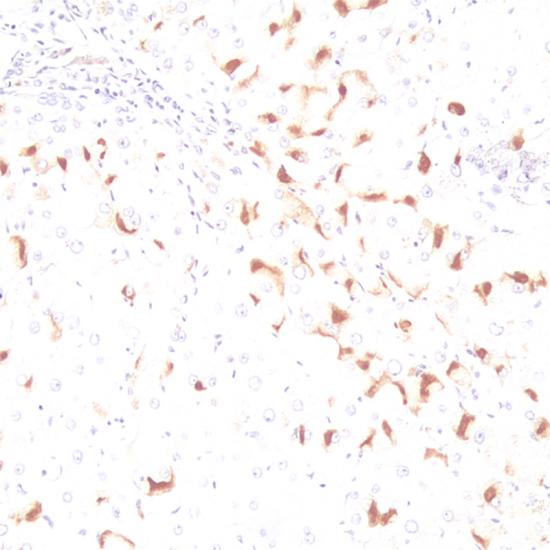

乙型肝炎病毒表面抗原(HBsAg)抗體試劑(免疫組織化學(xué)法) 閩廈械備20190049號(hào)

• 陽性部位:

細(xì)胞漿

• 陽性對照:

乙肝

此抗體與乙肝病毒表面抗原反應(yīng),主要用于標(biāo)記乙肝病毒感染的組織,也可用于肝硬化、肝癌及乙肝病毒感染等方面研究。